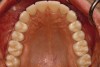

Fig 13. Prosthetic phase completion. Maxillary occlusal view. Note arch form change without compromise to the buccal alveolar bone and periodontal phenotype.

Figure 13